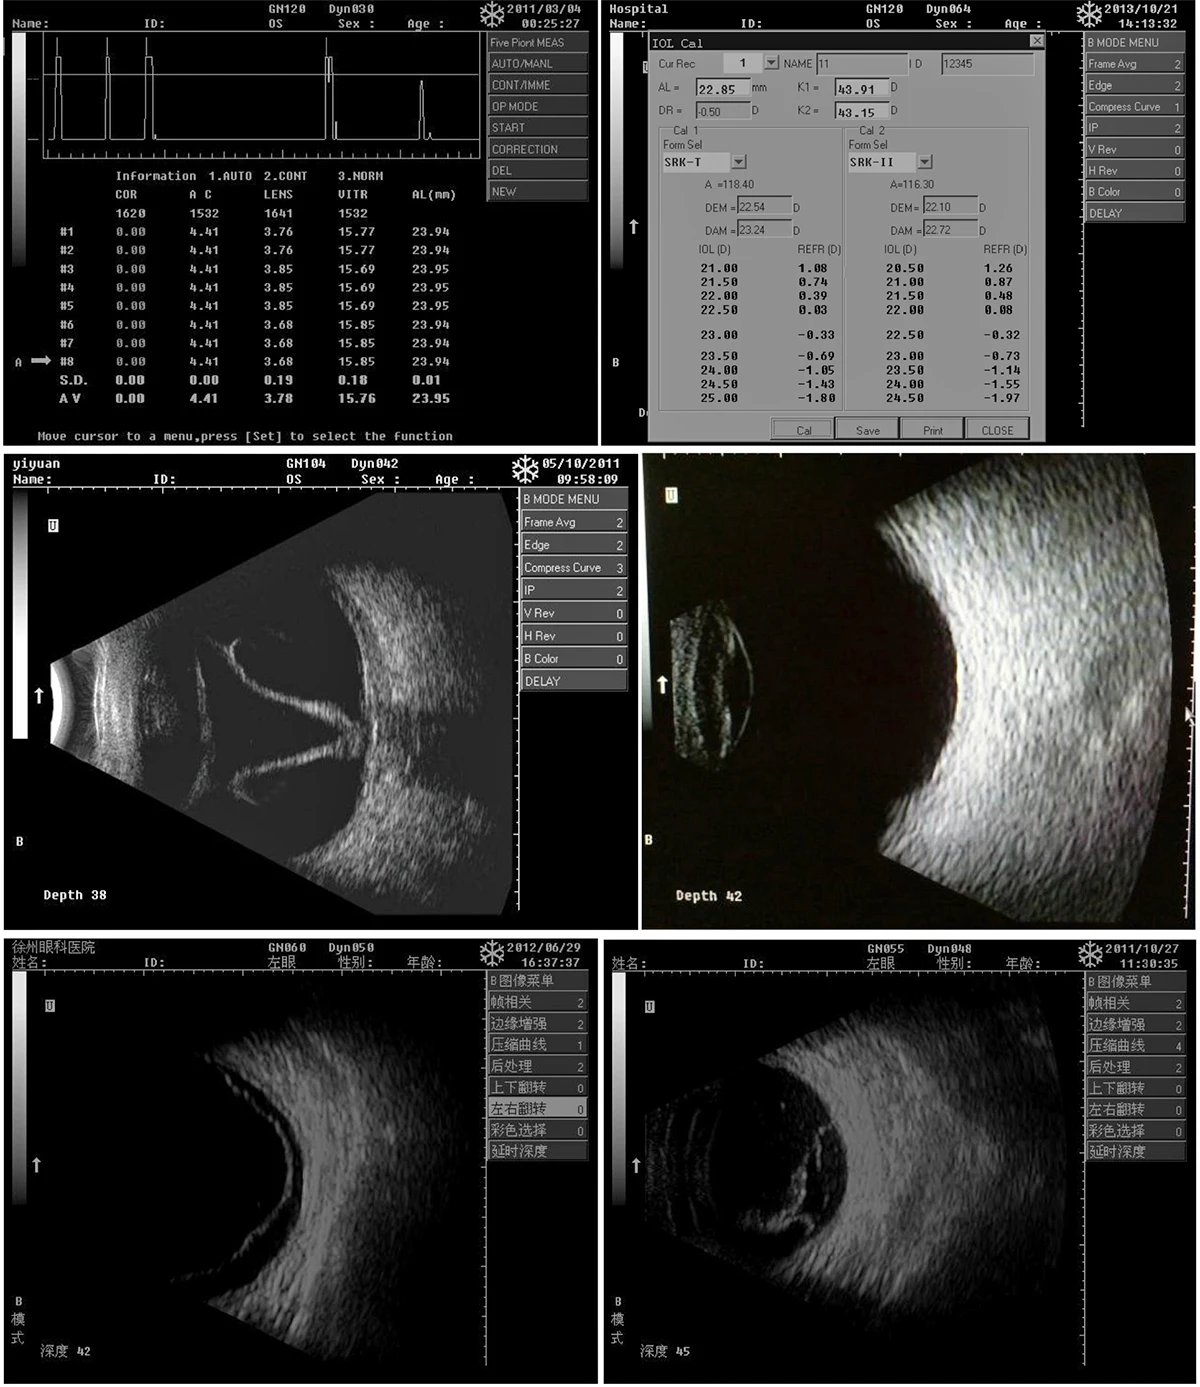

眼部b超常见病的图像及诊断

图片尺寸640x527